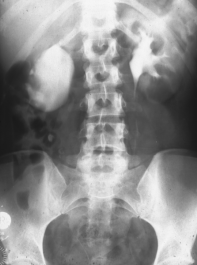

Rechtsseitige Ureterabgangsstenose mit deutlicher Hydronephrose. Behandlung mit Ureterabgangsplastik nach Anderson-Hynes (Abbildung 19).

• Abbildung 19:

1. Rechtsseitige Ureterabgangsstenose mit deutlicher Hydronephrose